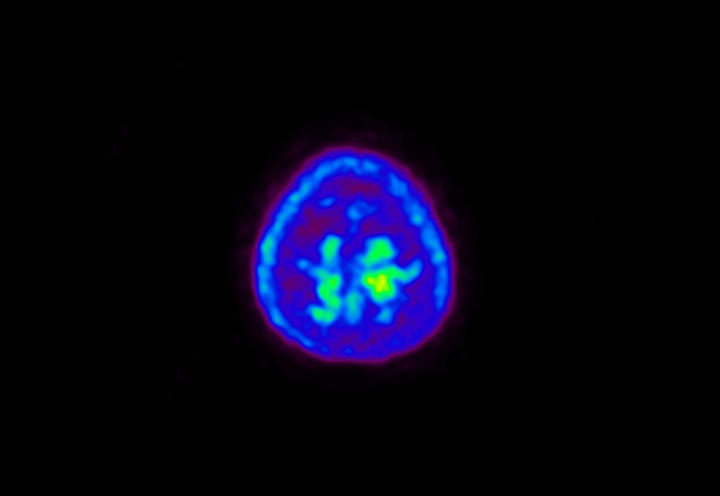

Head / Case5 : Amyloid

Coronal

Courtesy : Kindai University Hospital

- Imaging protocol

- Injected dose: 4.27 MBq/kg, 18F-Flutemetamol

- Uptake time: 99 minutes

- Scan time: 20 minutes